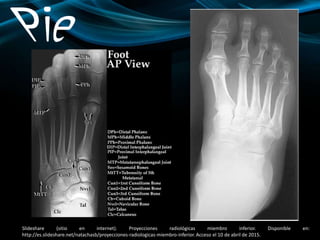

PROYECCIÓN AP (Proyección dorsoplantar)

II. RAYO CENTRAL Y COLIMACIÓN

IIA. RAYO CENTRAL:

 Un arco elevado requiere un ángulo

15° y un arco bajo más próximo a 5°

 Angular el RC 10° en sentido posterior,

cefálico (hacia el talón), RC

perpendicular a los metatarsianos.

 Dirigir el RC a la base del tercer

metatarsiano.

 SID mínima = 100 cm.

IIB. COLIMACIÓN:

 Colimar a los bordes externos del pie

en los cuatro lados.

III. CRITERIOS DE EXPOSICIÓN:

Se visualizan unos bordes y un patrón trabecular

nítidos de las falanges distales y de los tarsianos

distales al astrágalo, sesamoideos

V. POSICIÓN DEL PACIENTE:

Paciente en supino; flexionar la rodilla y colocar la superficie

plantar (planta) del pie afectado plano sobre el chasis (RI).

VI. POSICIÓN DE LA REGIÓN ANATÓMICA:

Alinear y centrar el eje longitudinal del pie al RC y al eje

longitudinal de la porción del RI que se expone.

VII. ESTRUCTURAS MOSTRADAS:

Se debe mostrar el pie en su totalidad,

con inclusión de todas las falanges y

metatarsianos, y del escafoides,

cuneiformes y cuboides.

VIII. PATOLOGÍA MOSTRADA:

Se muestra la localización y extensión de

las fracturas y alineación de los

fragmentos, hallux valgus, alteraciones

en el espacio articular, derrames de

partes blandas y localización de cuerpos

extraños opacos.